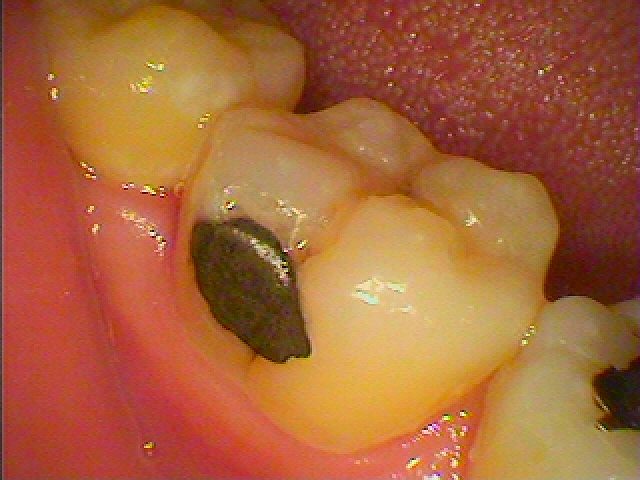

昔のアマルガムが適合不良となっています

セレックセラミックにて修復しています

綺麗に仕上がりました